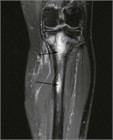

病態

1. 骨髄炎とは、細菌などが骨髄に感染したことにより起きる感染症である。血行性のほか、外傷や周囲の組織などから直接感染することがある。